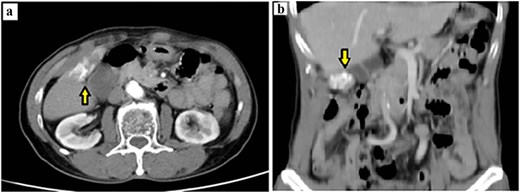

Laboratory tests showed normal liver function. White blood cell count was 8.61 k/μl (lymphocytes 22.1%). Tumor markers (CEA, CA 19-9, and AFP) were within normal limits. Chest radiography showed no active pulmonary lesions. Contrast-enhanced abdominal computed tomography (CT) demonstrated a bilobed gallbladder. In the distal (fundus) compartment, a 2 × 4 cm calcified mass was identified with adjacent wall thickening up to 4 mm (Fig. 1a and b). Multiple gallstones were present, with the largest measuring 11 mm. A gallbladder tumor with concomitant cholelithiasis was suspected. Because malignancy could not be excluded, laparoscopic cholecystectomy with intraoperative frozen section was planned, with preparedness to proceed to open radical cholecystectomy with hepatic wedge resection and hepatoduodenal lymphadenectomy if carcinoma was confirmed.

Preoperative contrast-enhanced CT demonstrating a calcified gallbladder fundus lesion suspicious for malignancy. (a) Axial CT shows a calcified mass at the gallbladder fundus with adjacent wall thickening (arrow). (b) Coronal CT reconstruction highlights the calcified lesion involving the gallbladder wall (arrow).